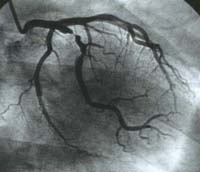

喫煙による冠動脈疾患のリスク 冠動脈造影のフィルム

冠動脈造影のフィルム

冠動脈の一部が極端に細くなっているのが判ります